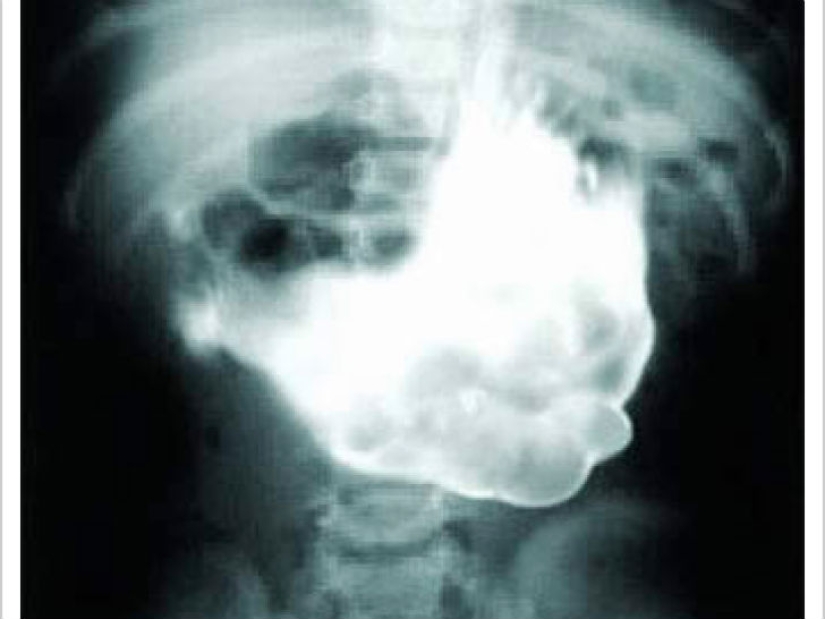

One little boy ate one part of a toy with a magnet at a time. When at last all the parts of the toy were in the boy's stomach, they connected.